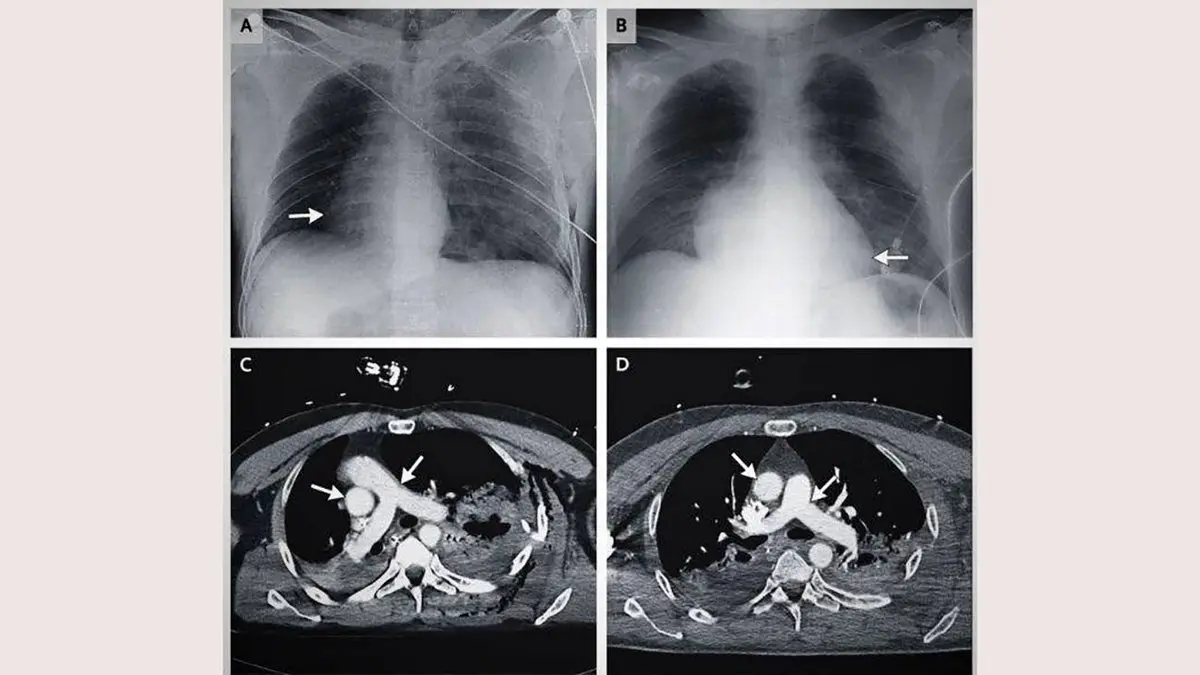

در ماه می سال 2014، یک اتفاق جالب در تاریخ پزشکی به ثبت رسید. قلب یک مرد بعد از تصادف با موتورسیکلت 90 درجه داخل قفسه سینه اش چرخیده بود و به سمت راست رفته بود. این گزارش در ژورنال پزشکی بریتانیا به ثبت رسانده شد.

سی تی اسکن ها نشان داد که قلب 90 درجه به سمت راست قفسه سینه رفته است.

زمانی که خواستند ضربان قلب او را اندازه بگیرند، متوجه شدند قلبش در قسمت راست بدن است و در سمت چپ، هیچ اثری از قلب وجود ندارد. سپس او را برای آزمایش اشعه ایکس و سی تی اسکن آماده کردند. سی تی اسکن هم دقیقا همین موضوع را نشان داد. این گزارش در مجله پزشکی به ثبت رسانده شد.

زمانی که اسکن کل بدن انجام شد، متوجه شدند که رگ های بزرگ و اصلی سرخرگ و آئورت، هر دو همراه با قلب به سمت راست رفته اند. این فرد مشکل ریه پیدا کرده بود و چندین شکستگی در دنده هم برایش اتفاق افتاد و به دلیل تصادف، طحال او هم آسیب دیده بود اما با وجود چنین آسیب دیدگی های شدیدی، باز هم زنده مانده بود، هوشیار بود و متوجه اتفاقات اطرافش بود.

پزشکان بعد از آزمایشات متعدد متوجه شدند که این اتفاق در حین تصادف رخ نداده است، بلکه چند دقیقه بعد از تصادف قلب این مرد چرخش داشته است. به این صورت که هوا از سمت ریه آسیب دیده به فضای قفسه سینه وارد شده بود و همین هوای بسیار زیاد، قلب را به سمت راست هل داده بود. سپس پزشکان هوای اضافی را از قفسه سینه مرد بیرون کشیدند.

جالب است بدانید که بعد از 24 ساعت، قلب این مرد به سر جای اصلی خودش برگشت. آزمایشات نشان داد که قلب این مرد کاملا سالم است و فقط تعداد کمی از رگ های خونی او به دلیل فشار خون حاصل از چرخش، دچار مشکل شده بودند.